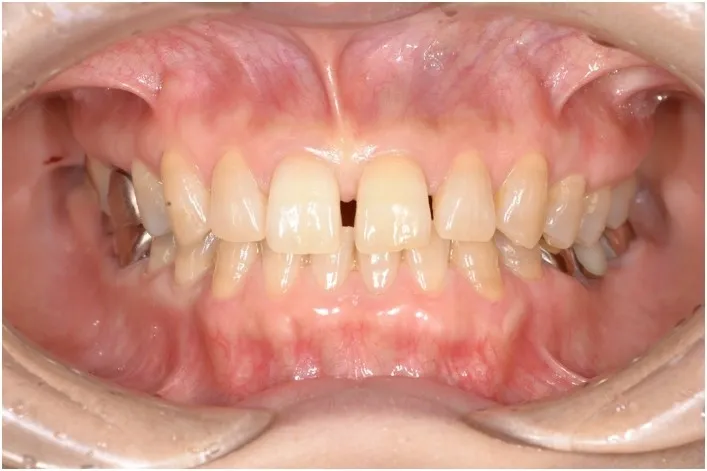

【治療前】